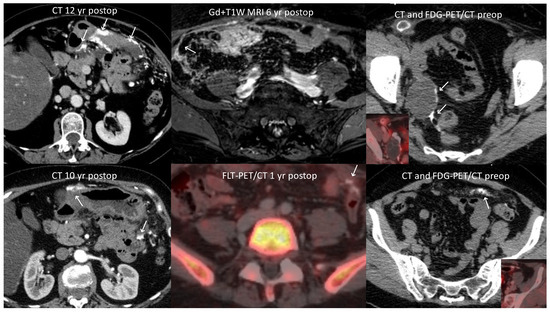

5.2. Radiology

| Imaging Modality | Characteristics | Articles |

|---|---|---|

| CT | Less pronounced density, uniform distribution of calcification | Hiromura [27] |

| FDG PET/CT | Increased metabolic activity | Bodnar [16], Dong [47], Chase [15] |

| Bone scintigraphy | Prominent calcification | Ranner [48], Radin [11] |

| MRI | Sandy or coarse granulated | Hiromura [27] |